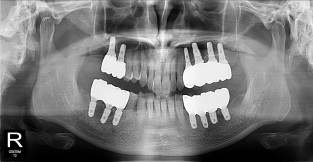

• 9

무치악

치료기간 : 2023-02-21 ~ 2023-10-21

1. 상기 x-ray 이미지 모두 동일한 해당 의료기관에서 진료한 환자입니다.

2. 상기 x-ray 이미지 모두 동일 인물의 것입니다.

3. 치료 전 이미지는 2023-02-21에 촬영했으며, 치료 후 이미지는 2023-10-21에 촬영하였습니다.

4. 상기 x-ray 이미지 모두 동일 조건에서 환자분의 동의를 받아촬영되었습니다.

* 임플란트 시술은 환자분의 상태(고혈압, 당뇨 등)에 따라 부작용이 있을 수 있으니, 반드시 전문의와 상담이 필요합니다.

* 임플란트 수술 부작용

: 수술 후 출혈, 교합, 통증, 붓기, 염증 등의 문제점이 발생할 수 있습니다.)